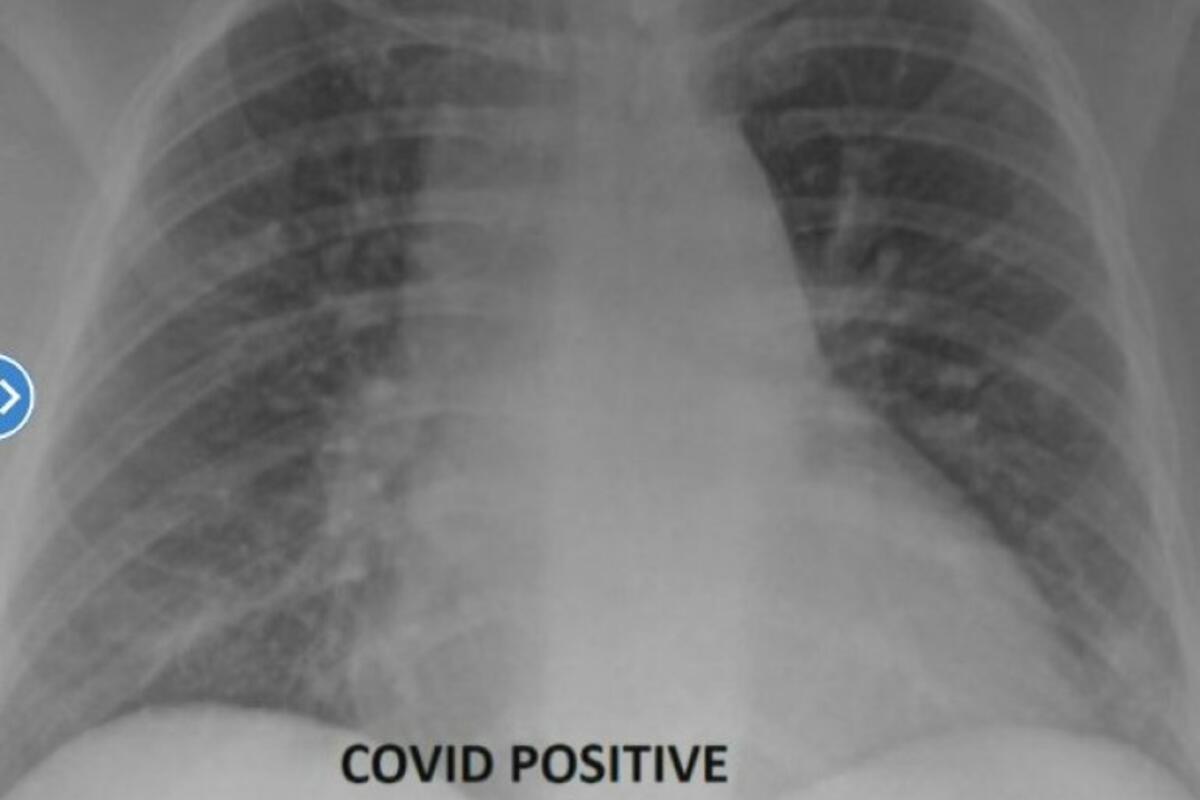

Koliki je značaj vakcine protiv kovida-19 stručnjaci u ovoj oblasti objašnjavaju mesecima unazad. Međuti, doktor Sem Durani, šef osoblja medicinskog centra “Deer Valley” odlučio je da na konkretnom primeru rendgenskih snimaka pokaže ljudima kako izgledaju pluća osobe zaražene kovidom koja nije vakcinisana i one osobe koja je vakcinu primila. Razlika je veoma očigledna i uočljiva.

“Jedini ljudi koji se zaista razbole su ljudi koji nisu vakcinisani. Oni često zahtevaju respirator i kiseonik, posebno oni pacijenti sa rendgenskim snimkom koji vidimo”, naglasio je doktor Durani za pomenuti britanski portal.

Kada su u pitanju oni pacijenti koji su neophodne doze vakcina primili, slika njihovih pluža daleko je jasnija i povoljnija.

“Snimak vakcinisanih pacijenata zaraženih pokazuje više protoka vazduha, pri čemu je veći deo pluća obojen u crno, što znači da nema ili ima izuzetno mala oštećenja”, rekao je doktor.

Nasuprot tome, slika snimka nevakcinisane osobe pokazuje da su pluća zagušena, što ograničava protok kiseonika kroz telo.

“Ako imate vakcinisanog pacijenta koji dođe u hitnu pomoć sa prodornom infekcijom, koji možda ima kratak dah i uradimo CT skeniranje, oni nisu ni približno tako loši kao nevakcinisani pacijenti”, dodaje doktor Sem Durani.